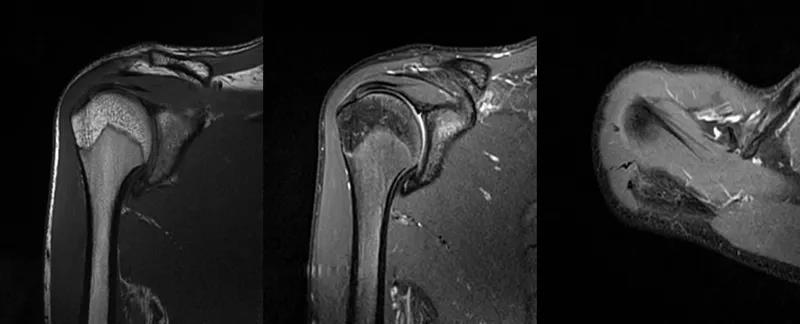

2、MRI检查MRI目前是诊断肩袖疾病中最常用的检查,可以直观的观察肩袖肌腱。

图21 斜冠状位(临床常用)a.T2,b.T1

图22 斜矢状位 a.冈上肌出口,肩袖诊断不如斜冠状位;b.冈上肌及肌腹脂肪浸润成度,评估手术与否

图23 横断位a.正常肩胛下肌;b.肩胛下肌损伤

图24 a.肩袖全层撕裂;b.正常MRI

图25 巨大肩袖损伤(冈上肌)